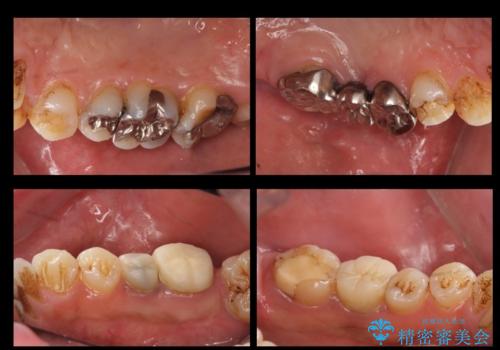

また、歯並びの矯正をするのではなければ、右上の八重歯は、犬歯を抜くか、奥に入っている歯を抜くかになるとお伝えしました。結果、根の長い犬歯を残して右上の前歯を抜歯しブリッジにしました。また、前歯の神経は極力取らないで治療を行いました。(結果神経を取る治療は前歯には行っておりません)

右下奥歯二本はインプラントにしました。(横浜桜木町歯科院長 大元先生による)

また、銀歯はすべてやり直しを行い、セラミックでやり替えを行いました。